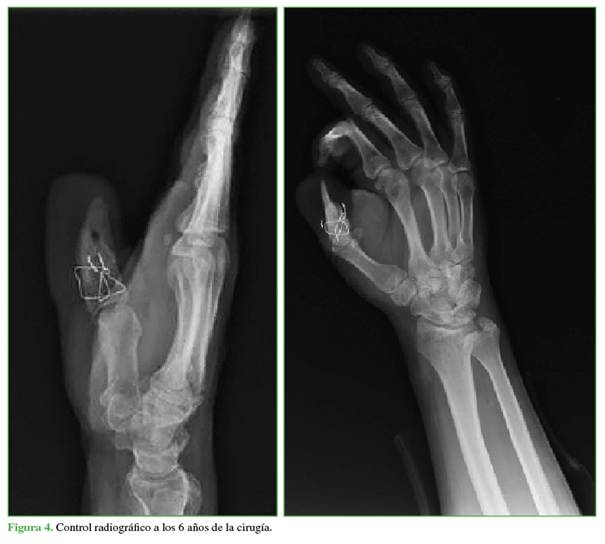

En las radiografías, se observa la remodelación ósea parcial por reabsorción con pérdida del 10% de la longitud del injerto, sin implicancias clínicas, ni lesiones por fragilidad (Figura 4).